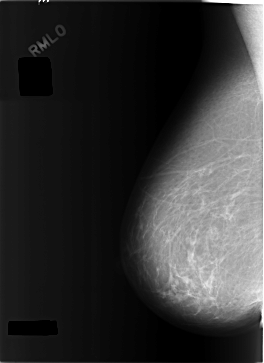

C_0301_1.RIGHT_MLO

RIGHT_CC LINES 5768 PIXELS_PER_LINE 3840 BITS_PER_PIXEL 12 RESOLUTION 50 NON_OVERLAY

RIGHT_MLO LINES 5800 PIXELS_PER_LINE 4216 BITS_PER_PIXEL 12 RESOLUTION 50 NON_OVERLAY